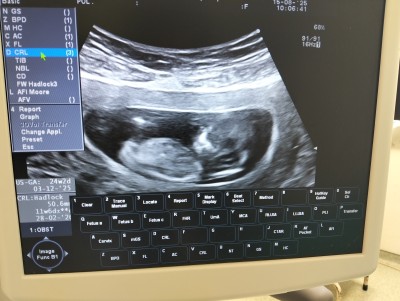

Kızlar bebeğim hep kendini gizliyor sizce nedir kıza benzetiyorlar

tahminleri alalım 🥺

Gebelik haftası 23